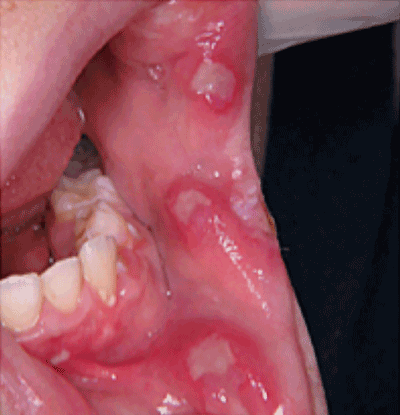

Motif de la consultation. Enfant de 10 ans adressé pour des ulcérations buccales douloureuses et récidivantes.

Examen clinique.

Il révélait plusieurs ulcérations infra-centimétriques, cernées par un liseré érythémateux. Les lésions étaient localisées sur la muqueuse non kératinisée jugale et labiale. La palpation des aires ganglionnaires cervicales mettait en évidence des adénopathies multiples douloureuses.